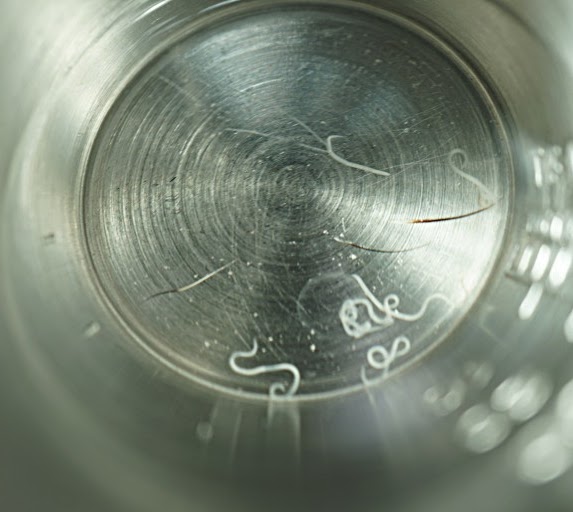

今回の感染した犬は体重17kgの中型犬です。お住まいは新青梅街道の北側、狭山湖よりとなります。目ヤニがで始めたとこのことで来院されましたが、眼検査と目ヤニの検査で東洋眼虫が確認されました。後日全身麻酔下で眼球洗浄、左右眼球から合計14匹の眼虫を取り除きました。

この後に、目ヤニの顕微鏡画像、麻酔下の眼虫摘出動画、摘出後の眼虫画像を掲載します。苦手な方はご注意ください。